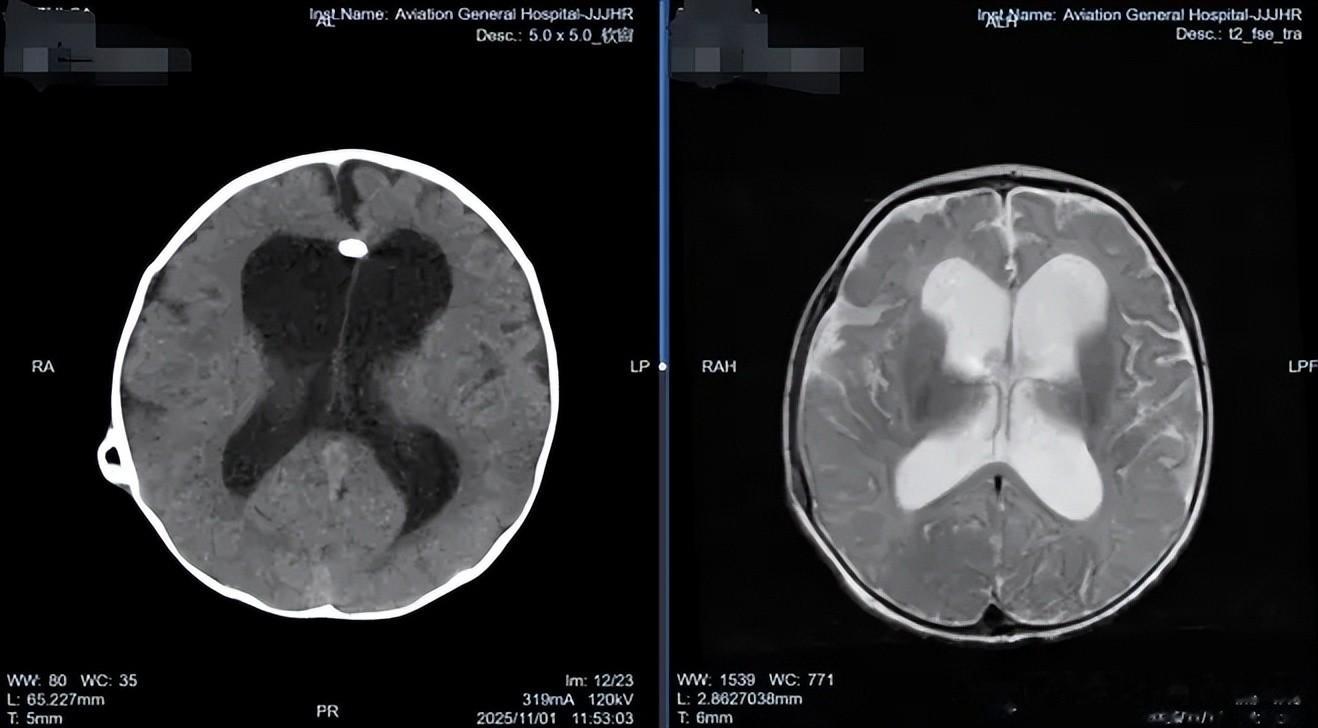

面对患儿的复杂情况,肖庆主任没有急于制定手术方案,而是凭借丰富的临床经验,首先深入了解孩子的全面健康状况,初诊断考虑颅内脑脊液异常,明确的颅内感染证据是治疗的关键。

随后于 2025 年 11 月 6 日在全麻下为患儿实施了神经内镜下第三脑室底造瘘术 + 原分流管去除术。术中留取原分流管管头培养,回报表皮葡萄球菌(+),这一发现证实了术前的感染判断,也解释了为何初次分流术后患儿症状未见改善。

肖庆主任指出,软性神经内镜能够对整个脑室系统进行全面探查,对脑积水的病因判断更为确切。在治疗方面,可根据脑室探查结果,对有出血、感染的脑室进行内镜下清洗手术,清除脑室内的“脏物”;对有明确梗阻的脑积水进行个性化疏通,如导水管成形、第四脑室流出道疏通等,使脑脊液恢复正常的生理循环。对于疏通困难者,可通过第三脑室造瘘、透明隔造瘘进行脑室内旁路手术,软性内镜下其瘘口位置选择更为灵活。此外,还可通过辅助脉络丛烧灼来减少脑脊液分泌以治疗难治性脑积水。该技术能清晰呈现深部病变,指导精确操作,最大限度减少脑损伤,降低并发症。